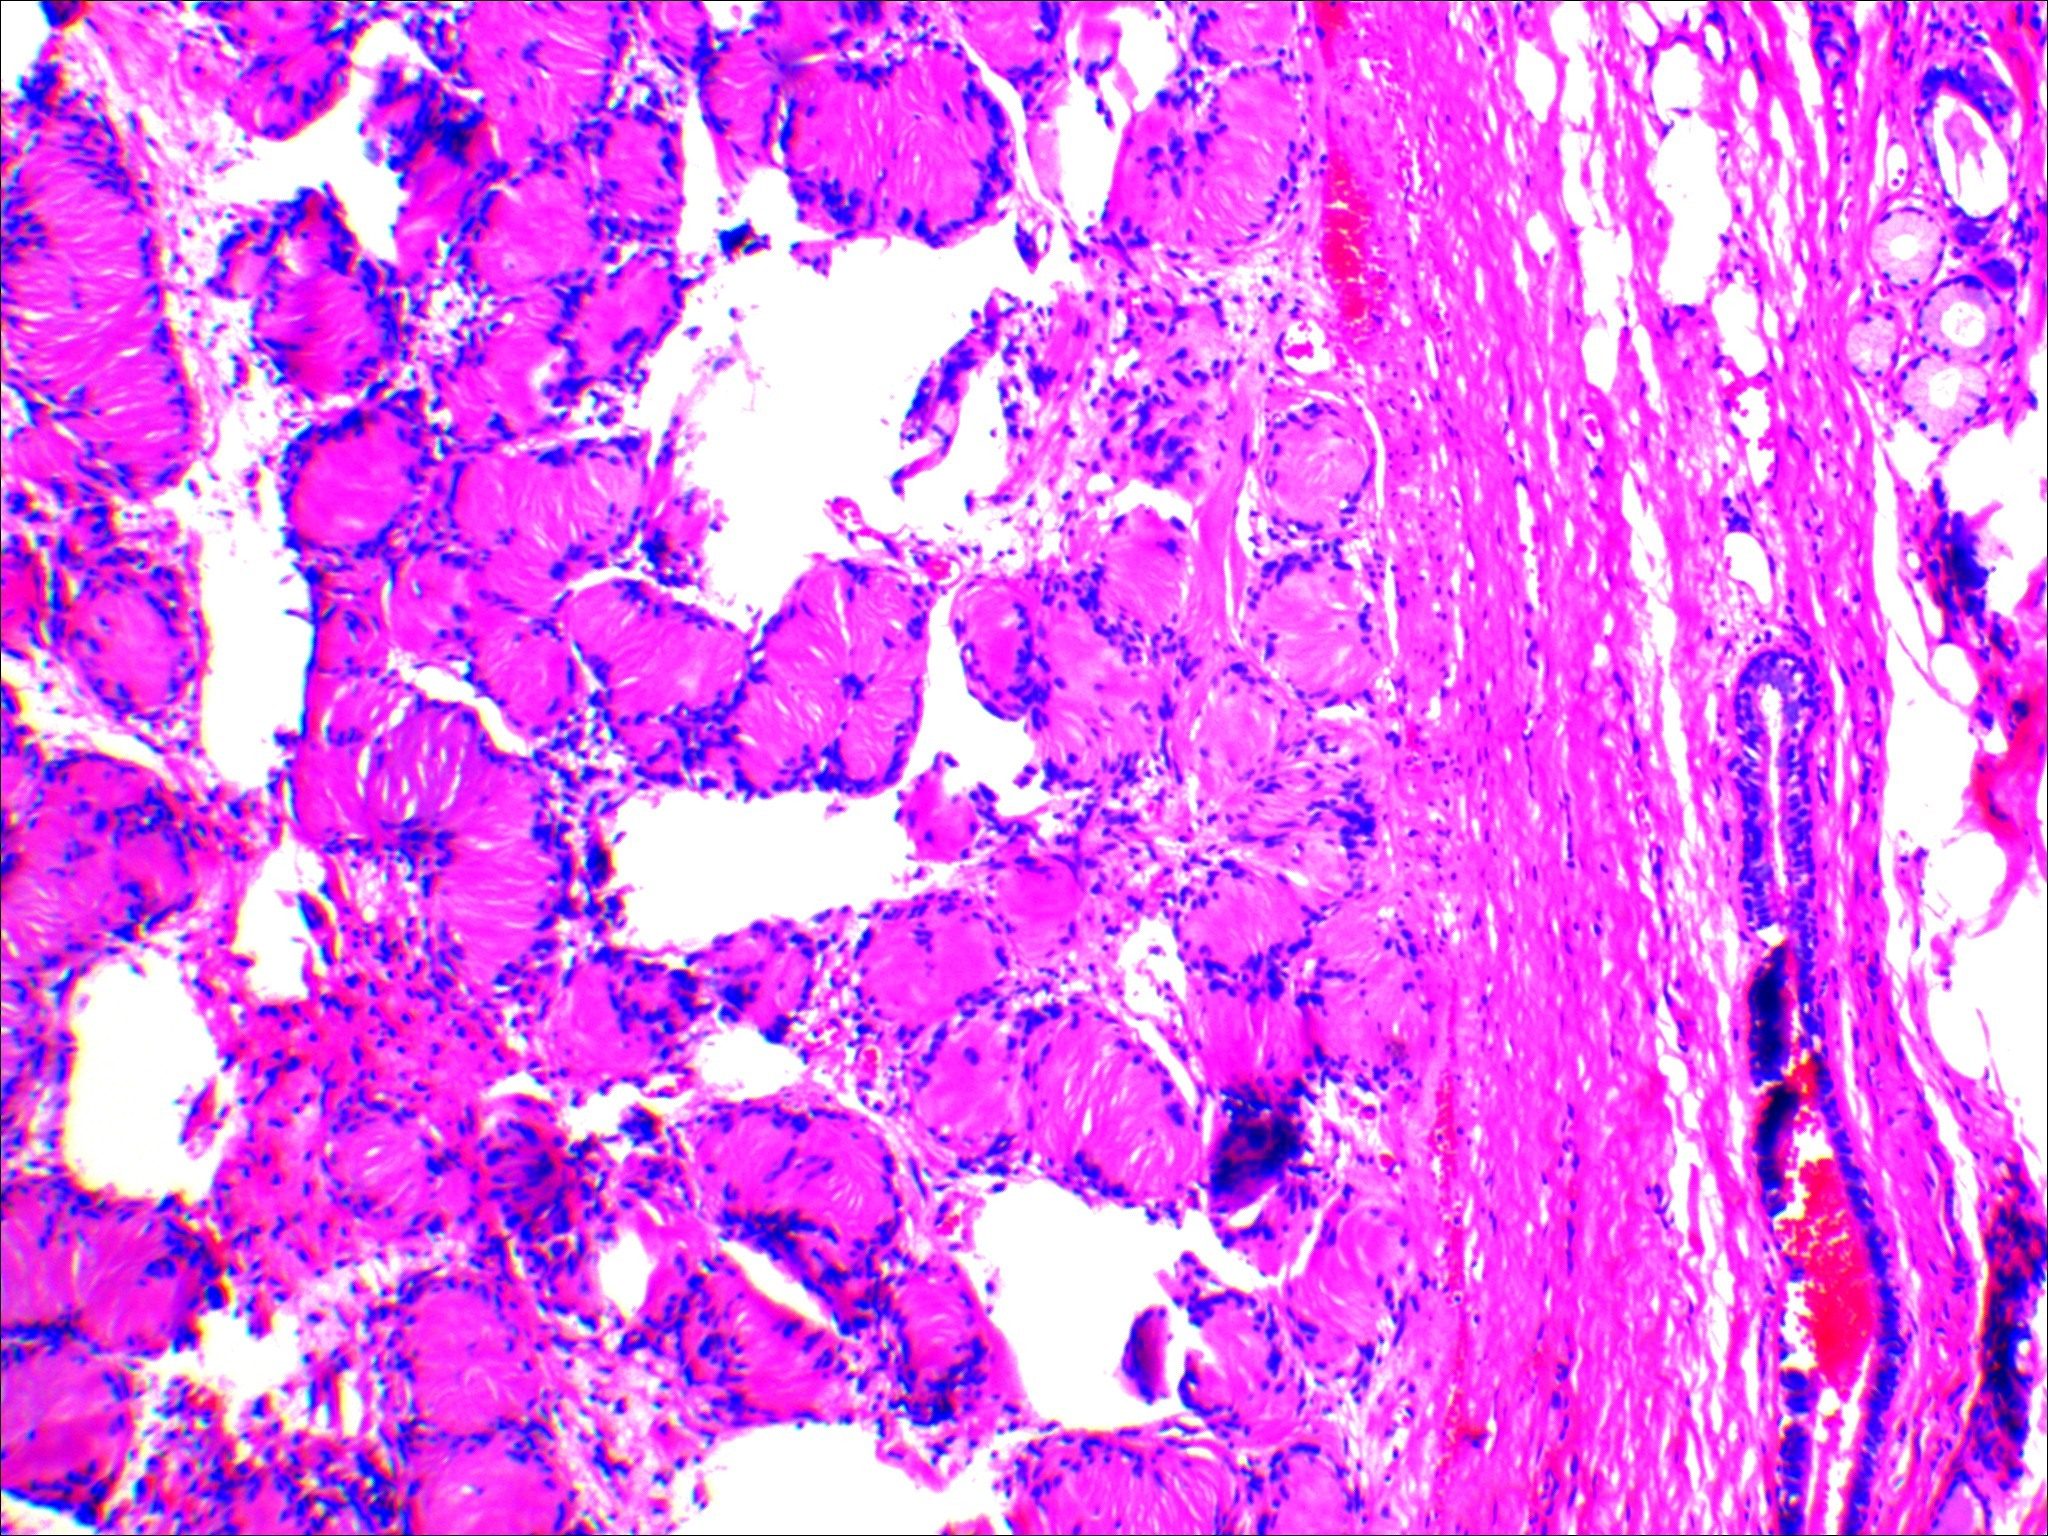

神经鞘瘤显微镜形态(图片来源于作者本人)

病理诊断:(左肺上叶结节)神经鞘瘤